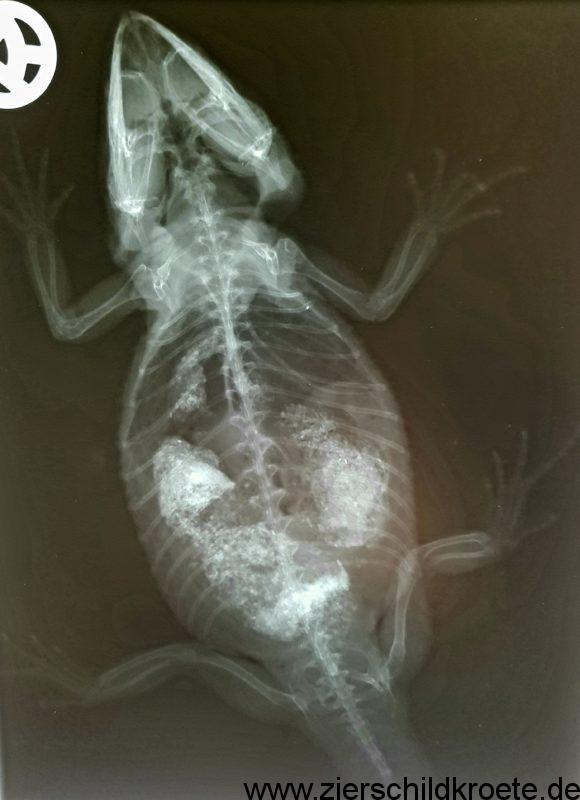

Je nach Beschaffenheit des Bodengrundes kann die Aufnahme gefährlich für Wasserschildkröten sein. Scharfkantige Steine bzw. scharfkantiger Sand kann den Darm perforieren und so sehr gefährlich sein. Bei Übermäßiger Aufnahme von Kies oder Sand kann es zu Verstopfungen kommen, die von alleine oft nicht verschwinden. Daher sollte man aufmerksam werden, wenn Wasserschildkröten viel vom Bodengrund ihres Aquariums aufnehmen.